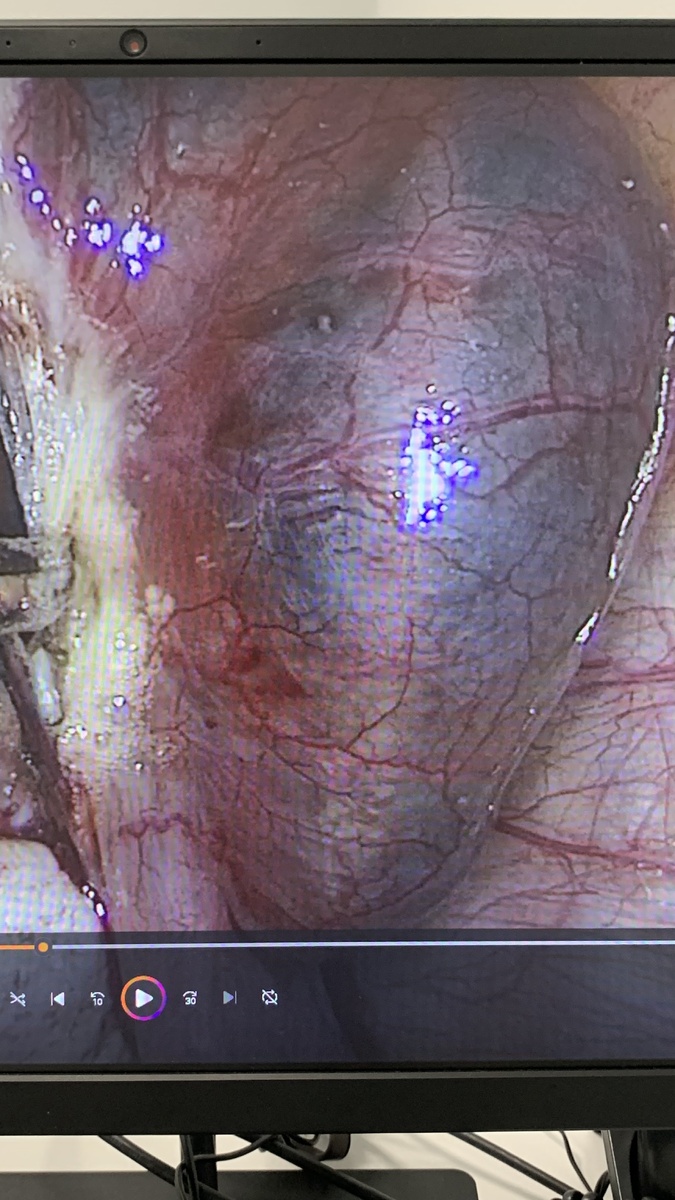

Внематочная беременность: 1 фото и 2 фото - беременность в маточной трубе; 3 фото - беременность в яичнике (очень редко встречается); 4 фото - беременность в углу матки (редко встречается). Опасность внематочной беременности - это кровотечение внутри живота. Проявляется сильнейшими болями, головокружением, бледностью кожных покровов, увеличением числа сердечных сокращений. Такие клинические ситуации являются скоропомощными и жизнь пациентки зависит от своевременной операции. #wmtmed, #гинекологхирург, #внематочнаябеременность, #лапароскопия

Внематочная беременность: 1 фото и 2 фото - беременность в маточной трубе; 3 фото - беременность в яичнике (очень редко встречается); 4 фото - беременность в углу матки (редко встречается).

Опасность внематочной беременности - это кровотечение внутри живота. Проявляется сильнейшими болями, головокружением, бледностью кожных покровов, увеличением числа сердечных сокращений. Такие клинические ситуации являются скоропомощными и жизнь пациентки зависит от своевременной операции.